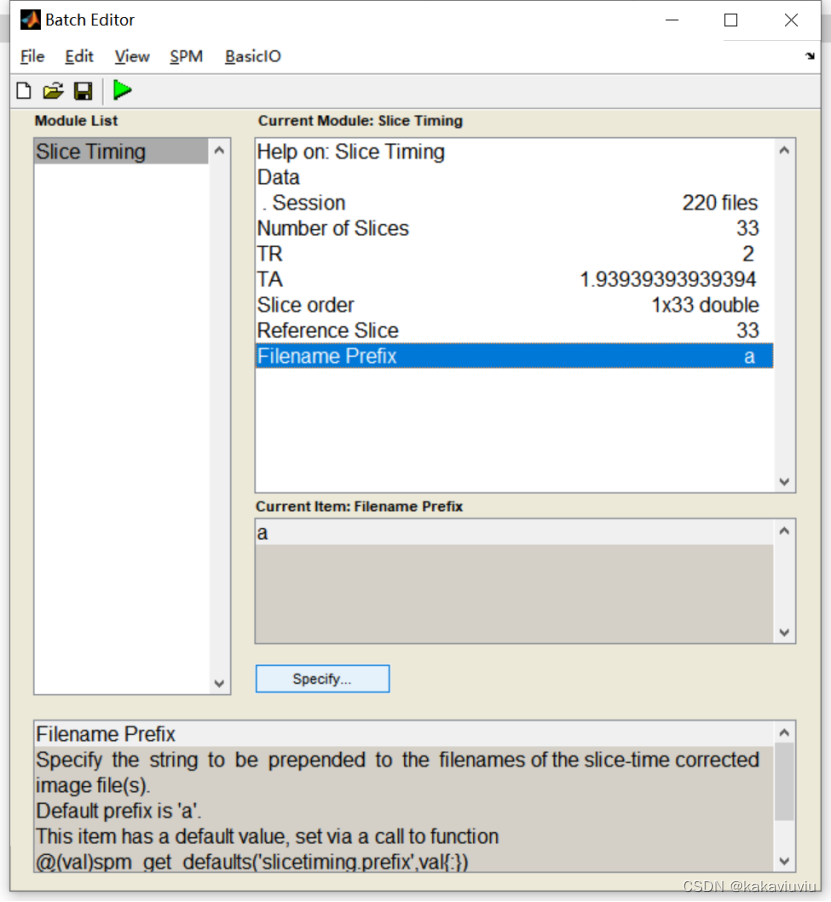

时间层校正后的文件带有a开头,表示校正后。

(2)第二步是A:时间层校正,

打开spm,点击slice timing--data--点击session

扫描层数:33层

填写TA

扫描顺序:1是首项,2是步长,33是尾项;两个等差数列之间用空格隔开(会自动判断是否结束)。翻译过来就是1 3 5 7层 ... 2 4 6 8层...这样的扫描顺序

参考层:中间层的层数(第33层)

填好了然后点绿色的符号开run!